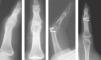

Las reducciones radiográficas de la fractura fueron aceptables desde el punto de vista anatómico en 78 (92,85%) casos. En 3 (3,57%) pacientes con fractura articular de la base de la falange conminuta hubo defecto de reducción de la fractura con una superficie articular corregida, en 2 pacientes (2,38%) no se consiguió corregir perfectamente la superficie articular debido a la gran conminución y a que los fragmentos óseos eran muy pequeños (referidos como malos resultados) y en un (1,19%) paciente con fractura de la falange proximal del cuarto dedo quedó una ligera diástasis del foco de fractura, tras tener un traumatismo en el dedo la fractura se desplazó y se lo intervino para colocarle una placa y tornillos (referido como mal resultado [figura 5).

Figura 5. Fractura oblicua larga de la falange proximal del dedo anular de la mano derecha. Fracaso de osteosíntesis percutánea. Nueva osteosíntesis con placa y tornillos.

Las complicaciones imputables a la técnica solamente se han observado en 3 pacientes, en uno de ellos la fractura no quedó suficientemente estable y al recibir el paciente un traumatismo sobre el dedo se desplazó y movió los tornillos, por lo que precisó una nueva intervención mediante osteosíntesis con placa y tornillos, con buenos resultados posteriores (figura 5). En 2 pacientes no se consiguió la reducción anatómica articular adecuada, aunque probablemente si se hubiera intentado la reducción abierta el resultado habría sido igual o peor debido al tamaño reducido y a la gran conminución de los fragmentos óseos.